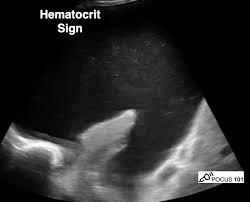

Ct (in a) and ultrasound (in b) revealing loculated pleural effusion. Chest ct and chest ultrasound images were also examined for parenchymal consolidation and the presence of lung necrosis or abscess. A parasternal long axis and subcostal views are shown. Note that the pigtail catheter in a is positioned below (rather than within) the loculated effusion, which explains why the catheter did drain any fluid until it was subsequently. Six patients with either malignant pleural effusion or empyema, in whom multiple conventional attempts at thoracocentesis were unsuccessful, were evaluated by ultrasound. 1 pleural effusion is defined as abnormal fluid collection in the pleural space. Note the presence of a fibrin strands extending from the lung to the diaphragm, resulting in loculations of the pleural effusion. Ultrasound can aid in the diagnosis of pleural effusion. A hemothorax on pulmonary ultrasound typically appears an effusion with a homogenous echogenic appearance 2 . The trocar technique is faster and easier. This is the shred or fractal sign. E7.8 loculated effusion loculated effusion. Both the trocar and the modified seldinger techniques can be used.

The success rate is low when the effusion is loculated and septated. The second effusion is loculated. Images were examined for the presence of pleural effusion and fibrin strands within the effusion. Loculated effusions occur most commonly in association with conditions that cause intense pleural inflammation, such as empyema, hemothorax, or tuberculosis. The thin arrow indicates the parietal pleural line. Ultrasound can aid in the diagnosis of pleural effusion. What are the different appearances of pleural effusion? Icu patients cannot sit up and the effusion layers posteriorly. Loculated effusions are difficult to confirm with chest radiograph, but ultrasound, computed tomography (ct), and even magnetic resonance imaging (mri) may be used to verify a localized collection of pleural fluid. Pleural effusion is assessed by ultrasound placing the transducer in the midaxillary line with the marker oriented toward the patient's head. Both the trocar and the modified seldinger techniques can be used. Pleural fluid studies are summarized in table 1. In each case, a subsequent thoracocentesis guided by ultrasound produced sufficient fluid to enable a diagnosis to be established.